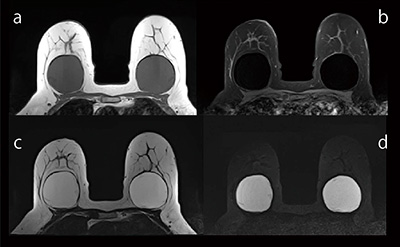

シリコンインプラント検査用の撮像シーケンス“PASTA-Si”を搭載。シリコン成分を高信号に描出することができるため,インプラントの内容成分がシリコンであるのか生理食塩水であるのかの識別,さらにはシリコンの漏れの有無を正確に確認することができます(図1)。

図1 シリコンインプラント画像

a:T1WI,b:脂肪抑制T2WI,

c:PASTA-Si,d:脂肪抑制PASTA-Si